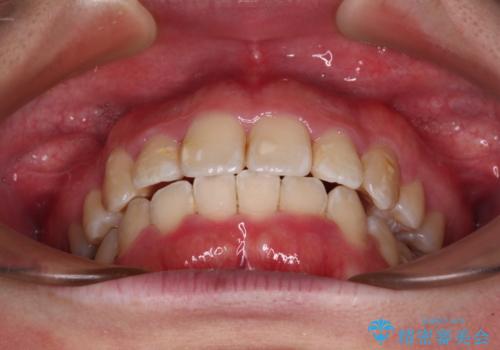

気になっていた八重歯は装置装着から3か月ほどで解消されました。

2年以内を目標として治療を開始しましたが、1年半ほどで終えることができました。